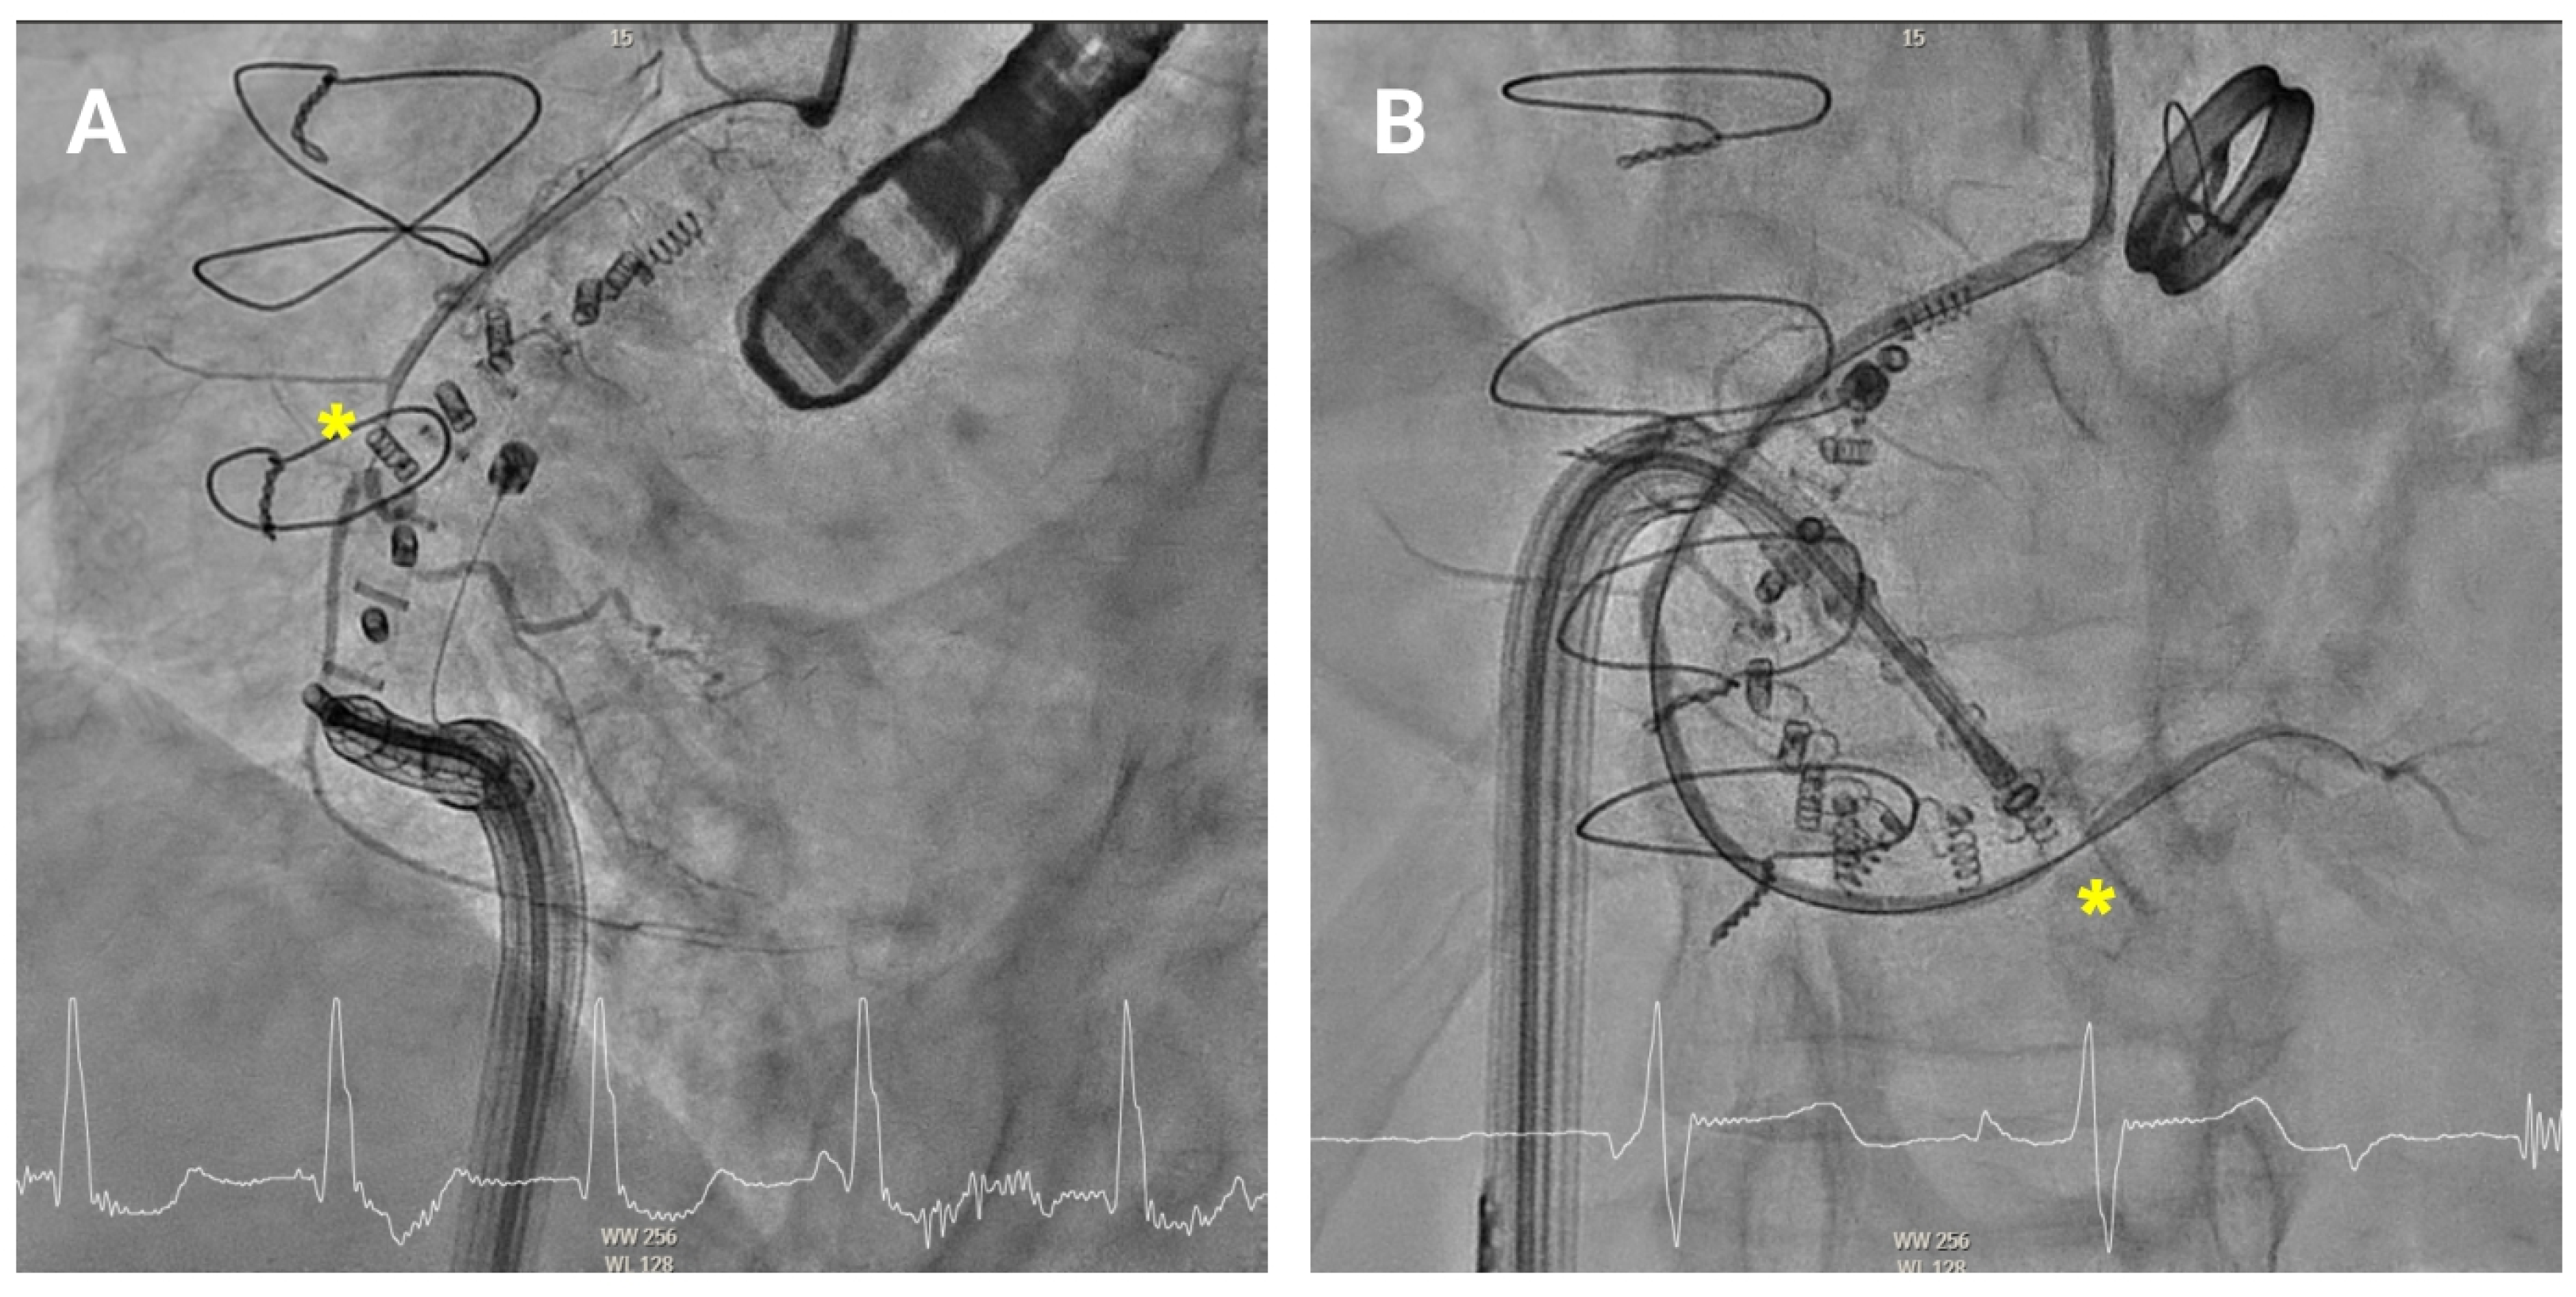

Anchoring along the posterior annulus (

Figure 6A) poses unique challenges due to its parallel alignment with the echo beam and distance from the probe. At this point, the device often needs to be curved in an angle of 90° between the IC and the TSS (“hooking”) to cross the RCA and properly reach the anchor points (

Supplemental Video S2). A mid-esophageal MPR view and a transgastric view at 150° provide a better view of this segment. RAO and LAO projections are employed to verify the alignment of the IC with the annulus and ensure there is no contact with unintended structures [

10,

11]. If loss of coaxiality or echo shadowing occurs, corrective actions include sheath repositioning, modification of LAO/RAO angles, or pre-shaping of the catheter curve.

4.3.5. Posteroseptal Commissure

Finally, as the band approaches the posteroseptal commissure (

Figure 6B), deep esophageal and mid-esophageal bicaval views ranging from 0° to 135° may facilitate visualization of the coronary sinus and the septum, which are critical during this phase [

11]. For final anchors placement, the RAO view helps confirming anchor security and alignment with the valve annulus, while avoiding any potential misalignment or overlap with other structures. Biplane imaging enhances alignment checks and reduces shadowing artifacts.

Figure 6.

Posterior tricuspid annulus anchoring. (A) Posterior annulus anchoring requires navigating anatomical complexity due to echo beam alignment and distance from the probe. A 90° “hooking” angle between the implant catheter and the transvenous steerable sheath is often necessary to overcome the right coronary artery and access the posterior annular region. Transgastric transesophageal view (150°) and upper esophageal retroflexed views aid visualization, while RAO and LAO fluoroscopic projections confirm alignment and proper catheter trajectory. (B) Final anchoring at the posteroseptal commissure using deep and mid-esophageal bicaval views (0–135°) for visualization of the coronary sinus and septum. RAO projection and biplane imaging help verifying proper anchor placement and avoiding overlap or misalignment with nearby structures.